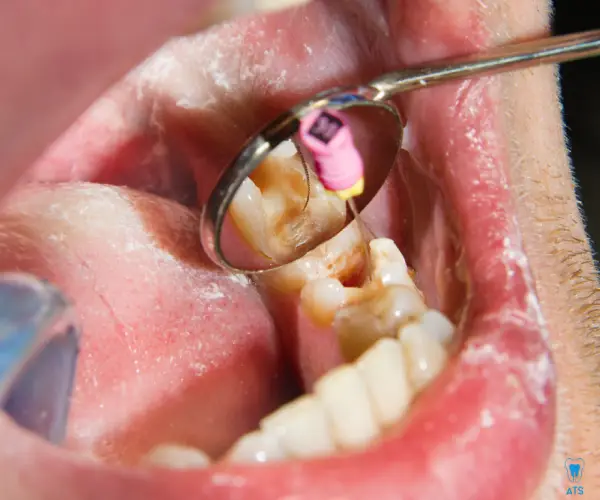

Tooth pain can affect your daily life and lower your confidence. While painkillers may offer short-term relief, they don’t solve the root cause. At ATS Dental Clinic, Thoraipakkam,Chennai, we specialize in advanced endodontic treatments, including painless root canal therapy to save your natural teeth. Our highly experienced endodontist,ensures precision, comfort, and long-lasting results with modern techniques.